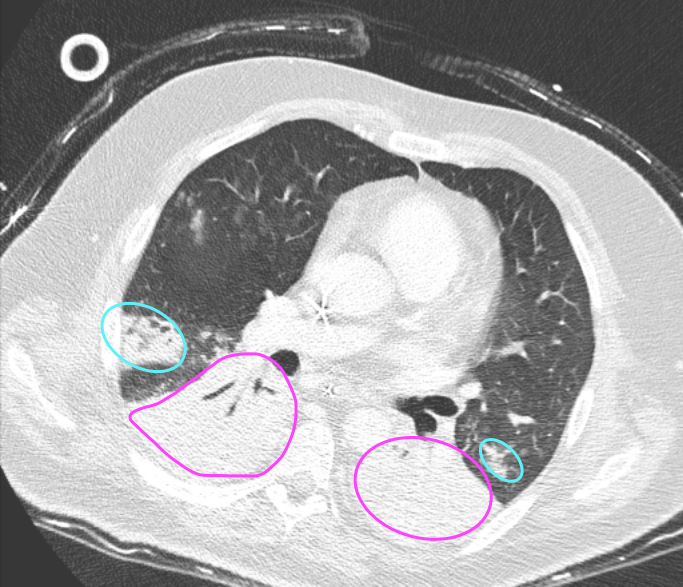

Refer to caption

(a) Patient 2

(b) Patient 9

(c) Patient 10

Figure 2: Exemplary transverse CT slices at the level of the EIT belt between 4th4th or 5th5th intercostal space defining the EIT reconstruction plane acquired in three of the studied patients. Markups indicate (yellow) ground-glass opacities, (magenta) dorsobasal atelectasis (with accompanying pleural effusion) and (cyan) pulmonary infiltrates.

For each patient, a single CT image was acquired with a Siemens Somatom or Philips IQon scanner at a pre-defined pressure state corresponding to end-expiratory lung volume (EELV) with an in plane resolution of 512x512 and a slice thickness of 2 mm according to routine clinical practice at the University Medical Center in Kiel. For all patients, EIT examinations were carried out using the Elisa 800 (Löwenstein Medical, Bad Ems, Germany) with the textile 32-electrode belt placed around the patient’s chest circumference in one slightly oblique transverse plane at the level of the 4th4th or 5th5th intercostal space, measured in the parasternal line. A brief overview over the patient cohort is given in Table 1, and Figure 2 shows exemplary slices of the chest CT at the height where the EIT belt was placed. Moreover, the shown slices highlight the regional heterogeneity of the lungs with bilateral infiltrates and pulmonary edema. In addition to the CT and EIT data, we used airway pressure, air flow, and esophageal pressure recorded during 10 breathing cycles of pressure-controlled ventilation.